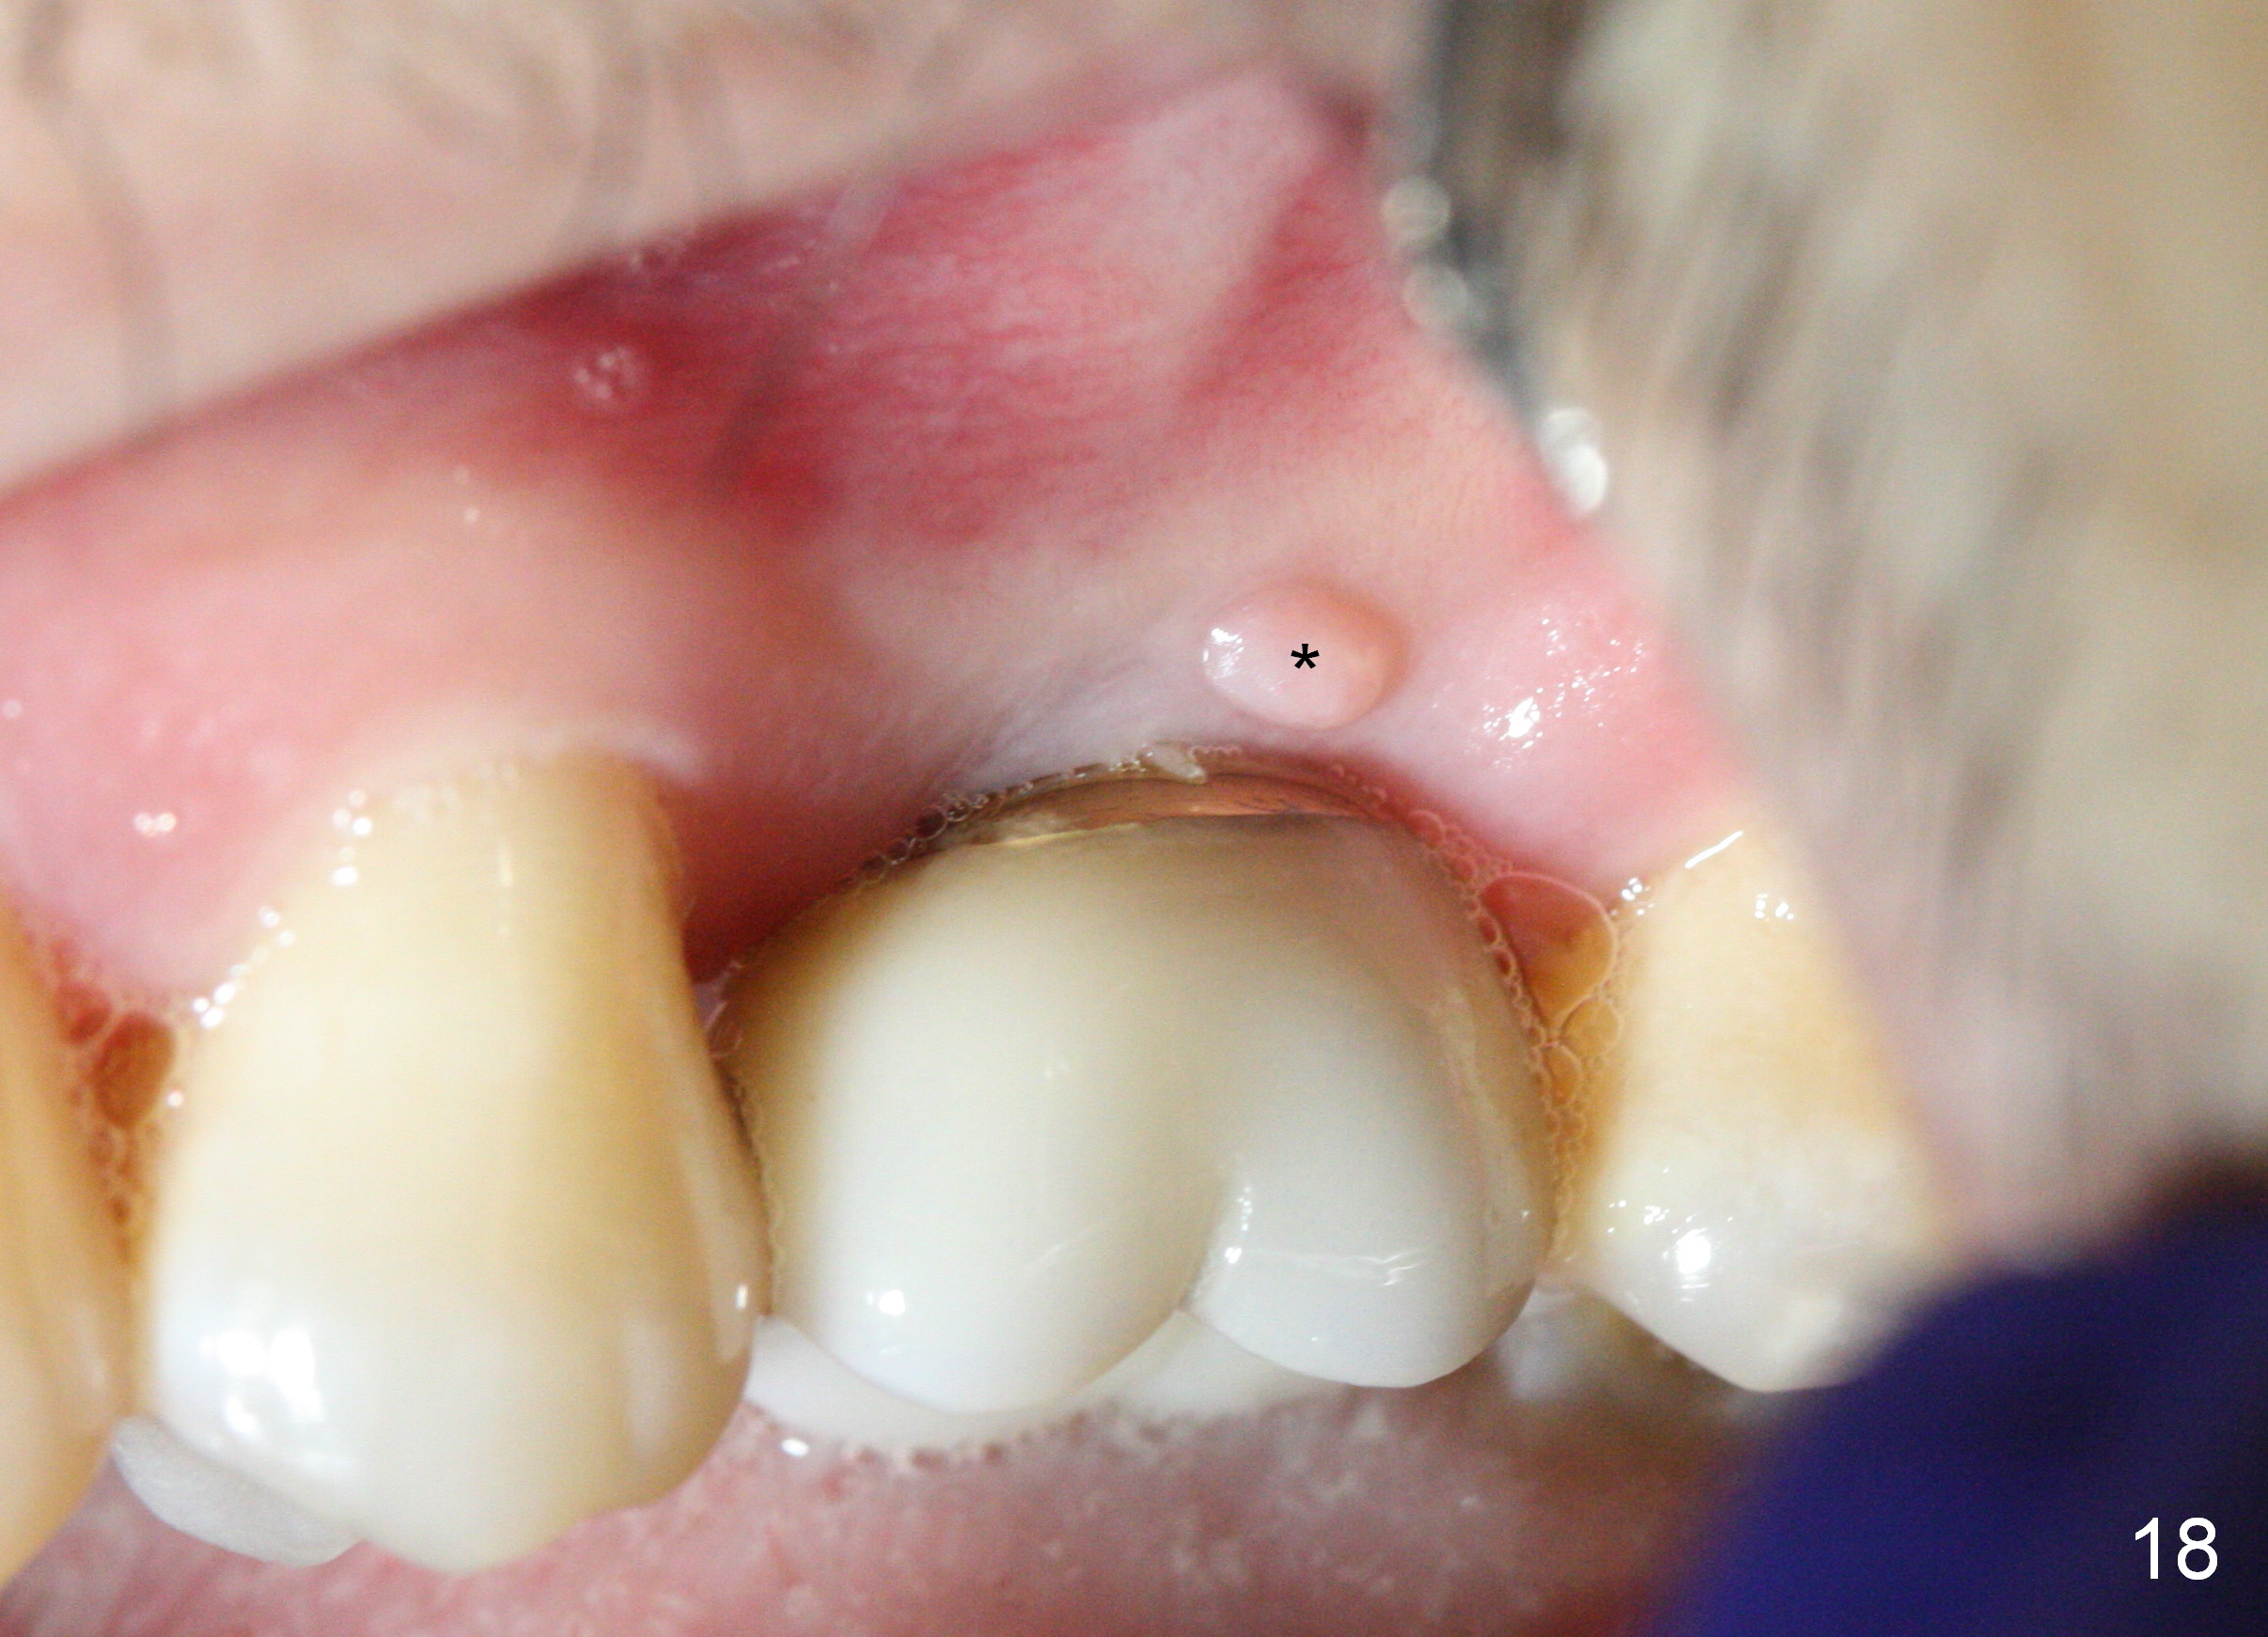

A 45-year-old man has lost the tooth #14 for a while (Fig.1); bone height is 5.4 mm. An extra wide and short implant is planned. Torus palatinus is large, suggesting that bone density should be high. A 6 mm tissue punch is chosen, but it is placed more palatal. If it were placed in the middle of the ridge, there would be no buccal keratinized gingiva (incision may avoid this issue). Additionally, the buccal portion of punch is made incomplete so that there is pedicle on the buccal side when the flap is raised (Fig.4,8: F). It is expected that the excess portion of keratinized tissue will form thick gingiva buccally. Osteotomy proves that bone is dense (Fig.2 (4.5x11 mm tap). Typical sinus lift is finished with placement of 6.4x6 mm (extra wide) bone-level implant (Fig.3, >55 Ncm). Following further torque, Fig.4 shows that the implant (I) is sub-gingival (<). Bitewings are taken to confirm that the implant plateau is at the crestal level (Fig.5,6 ^). PA shows sinus lift (Fig.7 *). The lingual aspect of the implant and healing abutment (H) is further bone grafted and covered by collagen dressing (Fig.8 *). The wound is protected with perio dressing. When the latter dislodges 7 days postop, the collagen dressing and bone graft are lost as well (Fig.10), while the buccal flap remains vital (Fig.9). The lingual exposed plateau should be able to heal normal. The collagen dressing should have been fixed in place by suture or as simple as a dental floss. There is mild nasal hemorrhage 1-2 days postop, possibly related to sinus membrane perforation and inability of Collagen Dressing to cover the perforation and contain the bone graft. When the patient returns for #9 implant placement in 3 weeks postop, the buccal flap reduces in size (Fig.11 *), while the palatal wound has healed with minimal exposure of the implant (Fig.12). Sinus graft remains in place 3 months postop (Fig.13); the buccal flap appears to have incorporated into a part of the gingiva (Fig.14). The bone density of the sinus lift appears to increase 10 days later when an abutment is placed (Fig.15 *). Although oral hygiene is pristine, there is apparent crestal bone resorption 12 months (Fig.16) and 20 months (Fig.17) post cementation, probably due to unfavorable crown/implant ratio and bruxism as well as pre-implantation bone loss (Fig.18,19). In contrast, an immediate implant in the same patient avoids pre- or post-implantation bone loss. In fact both the soft (Fig.20) and hard (Fig.21) tissues remain healthy 2 years 8 months post cementation. The sinus lift remains 3 years 8 months post cementation (Fig.22), while the crestal bone loss persists. The patients keeps complains of food impaction distal associated with bad smell 4 years 1 month post cementation. In fact the distal proximal contact is within normal limit. The bad smell is probably due to crestal bone loss (Fig.23 (pan), 24 (CT) *) and periimplantitis. Bone graft, PRF and Cytoplast membrane will be needed and fixed in place with long healing screw. When the patient returns for crown redo, he also reveals floss related gingival hemorrhage. There is pain associated with palatal sulcus probing with light gingiva erythema. Review of CT coronal section shows possible palatal (Fig.25 P) bone loss (*).